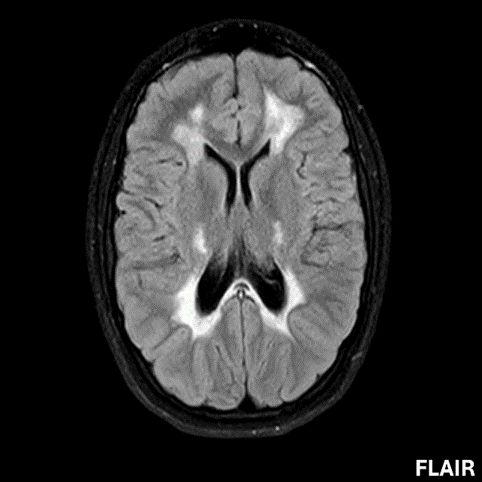

- A) Aksiyel T2A ve koronal T2A sekanslarda sentrum semiovale, korona radiata ve bazal ganglionlar düzeyinde bilateral frontoparietal derin periventriküler beyaz cevherde birleşme eğilimi gösteren hiperintens gliotik sinyal değişiklikleri (oklar) ve aksiyel T2A serilerde servikal spinal kordda posterior kolonda, lateral kesimlerde sinyal artımları (oklar) izlendi.

- B) Kontrastsız T1A serilerde tarifli alanlarda hipointens (oklar) görünüm izlendi. Kontrastlı T1A serilerde bu düzeyde (oklar) kontrastlanma artışı izlenmedi. Diffüzyon ağırlıklı serilerde belirgin diffüzyon kısıtlaması (oklar) görülmedi.

- Etkilenen bölgelerde T1’de hipointens, T2/FLAIR’da hiperintens sinyal değişiklikleri izlenir. DWI’de lezyonların periferinde kısıtlı difüzyon görülebilir. MRS’de beyaz cevherde laktat artışı saptanabilir, ancak bu her hastada mevcut değildir.